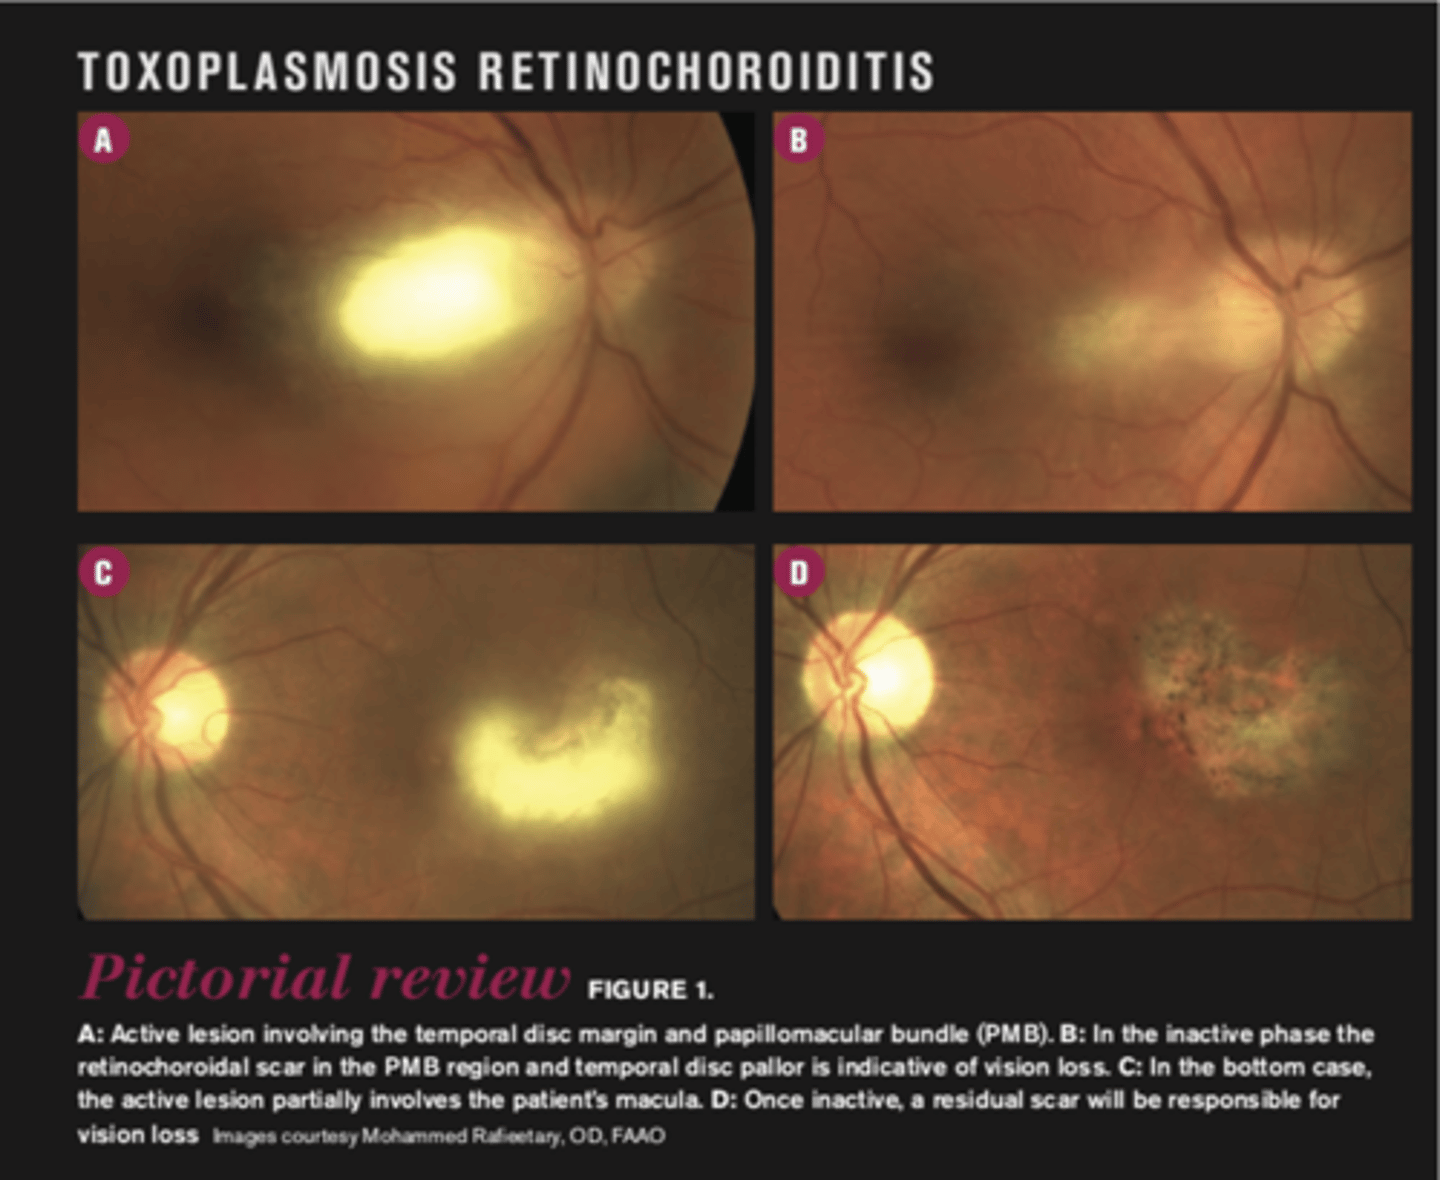

What finding of toxoplasmosis is seen in A/B?

retinitis turns into hazy scar with nerve pallor

What finding of toxoplasmosis is seen in C/D?

scarring overtime with VA loss/scotoma